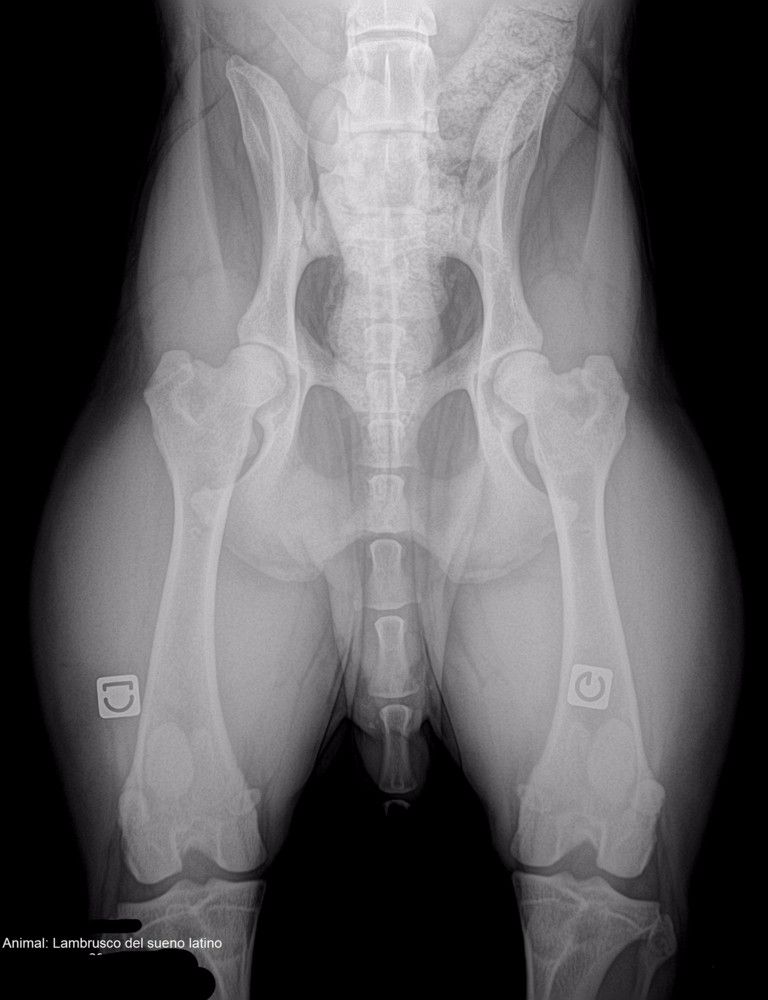

Radiographie hanches

Compte rendu officiel Dysplasie coxo-fémorale

A.D.N. : identifié + filiation parenté BAER TEST (surdité) : +/+ entendant bilatéral Dysplasie coxo-fémorale : A/A officiel Dysplasie des coudes : 0/0 officiel |